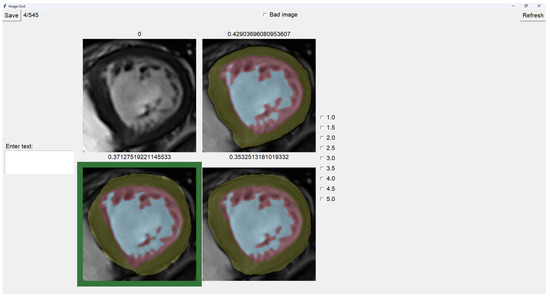

The program presents four images on a grid, as shown in Figure 5. The raw image is presented in the top-left corner, while the other three images are segmentations obtained differently. These three images are randomly placed in each iteration to ensure that this is a blind test.

On top of each image, we show the percentage of image trabeculation for the given segmentation (Equation (1)).

Again, we use a muted color scheme to make the colors distinguishable for colorblind people. The External Layer is olive, the Internal Cavity is cyan, and the Trabecular Zone is rose.

To select an image, you have to left-click on the image, and then a green box appears around the selected image (see Figure 6). On the right, we can choose a mark of 1–5, indicating how good the image is. Table 1 shows the subjective evaluation scale proposed in [23]. Finally, we can save it, which automatically brings up the next batch.

In addition, we can give feedback in the textbox on the left. We can also indicate whether the quality of the image is bad by selecting the checkbox at the center top.

The three images presented (see Figure 5 and Figure 6) are obtained using the following methods:

• Original targets: QLVTHC output [11].

• Blob-selection method: We compare the cross-validation method (Section 2.1) for improving images to the QLVTHC method on the image fixer. We improve the images only by choosing the best blobs based on their differences.

• Manually fixed method: We manually fix 100 images by coloring on the image fixer (left-click). We perform the cross-validation method on these 100 fixed images and continue manually fixing 400 more images using these outputs as a new base.